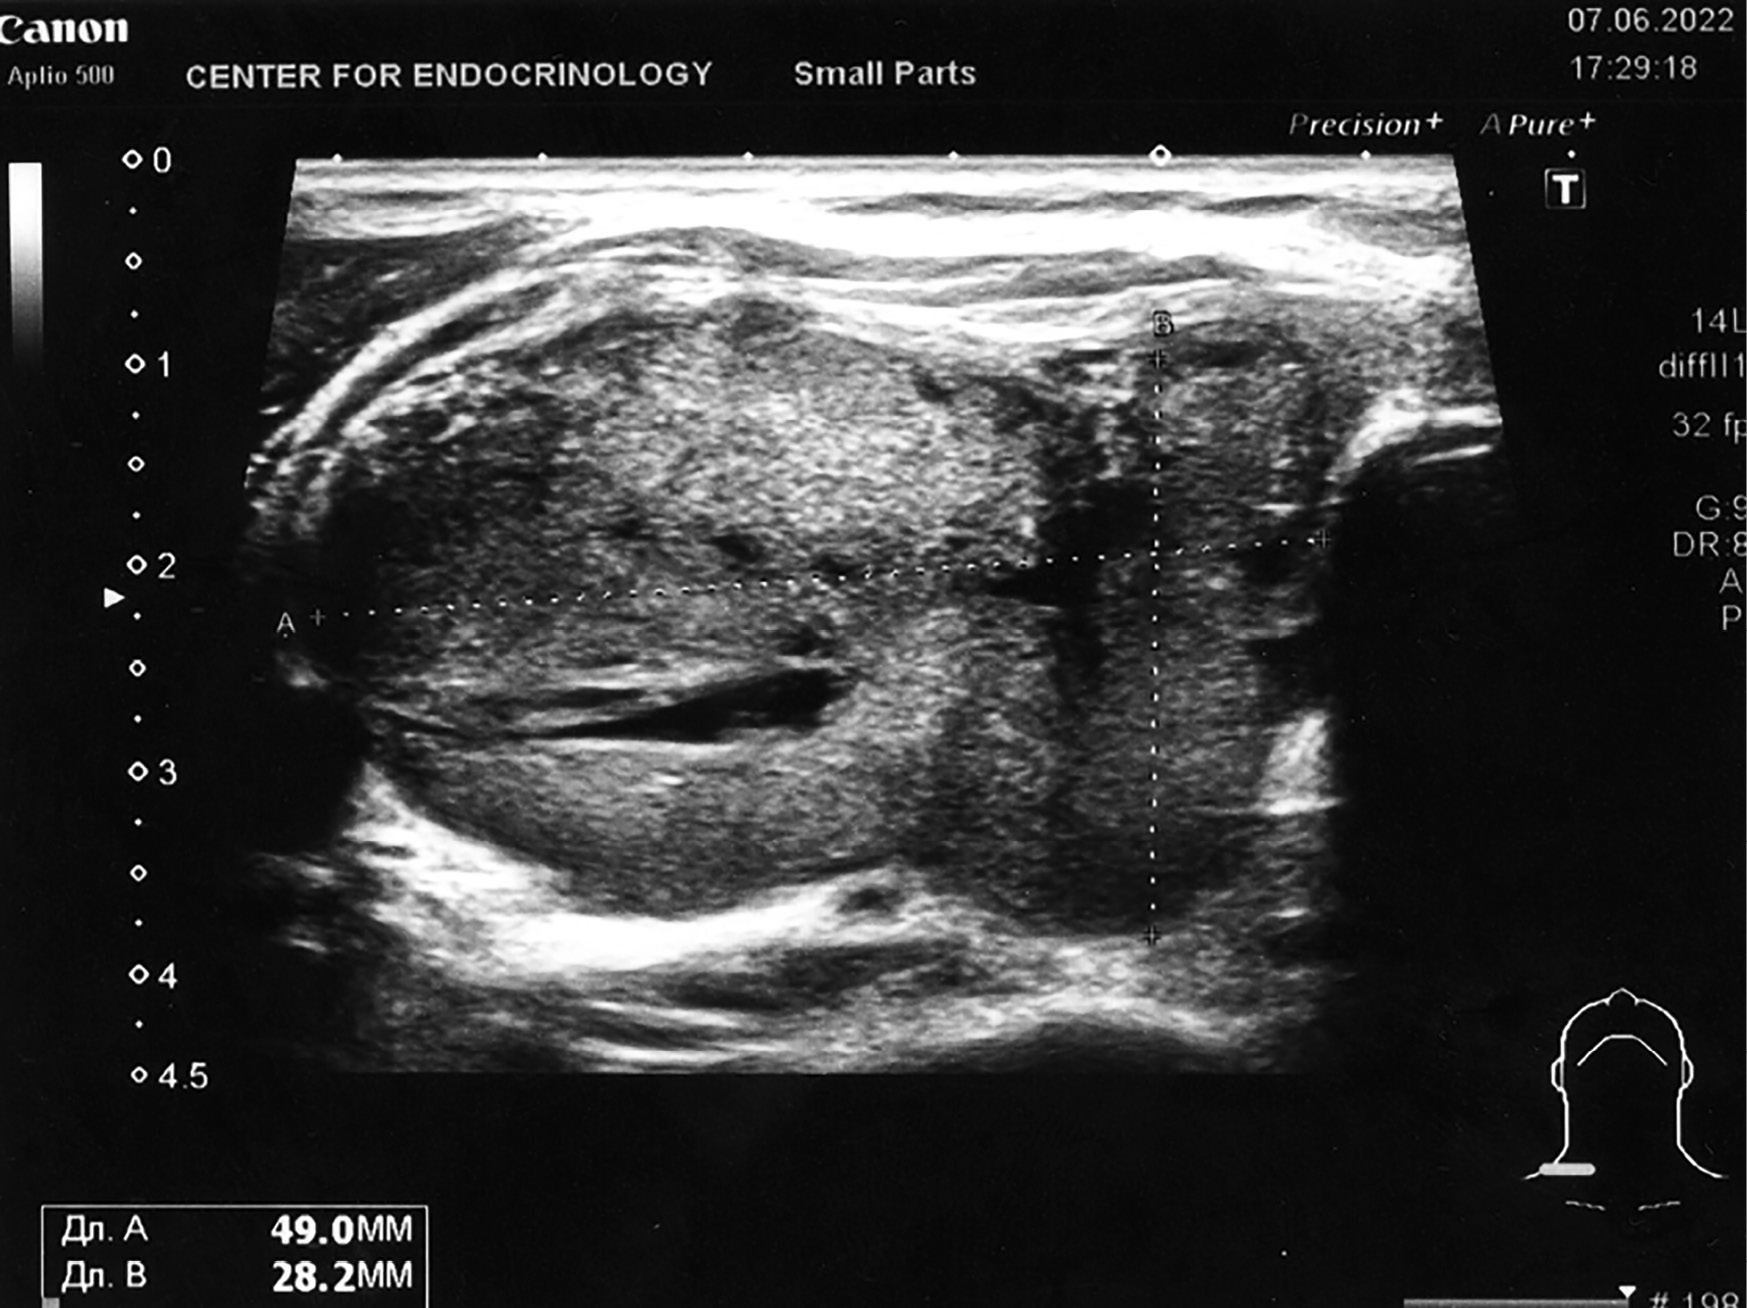

1. Рисунок 1. Ультрасонограмма ЩЖ. В правой доле ЩЖ определяется новообразование с нечеткими контурами пониженной эхогенности, анэхогенными зонами и кальцинатами в капсуле. | |